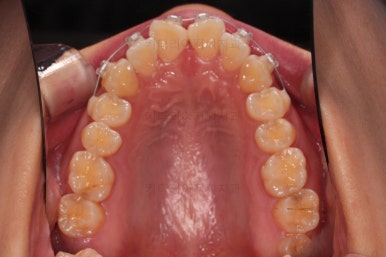

1. 초진

초진 시 입안의 모습입니다.

어금니 쪽은 약간 삐뚤긴 하지만 꼭 교정해야 할 정도는 아니고, 불편감 없이 비교적 잘 맞물리는 상태였습니다.

다만, 앞니ㅉㄱ이 공간이 부족해서 중간 치아들이 많이 회전되어있는데, 이를 환자분들의 표현에 따르면 "나비치아" 라고 부릅니다.

위아래 중간 앞니가 모두 나비치아처럼 되어있고요.

윗니가 아랫니보다 앞쪽으로 나와 있는 모습에 아래앞니가 윗니쪽으로 깊숙이 올라간 "과개교합" 양상을 보였습니다.